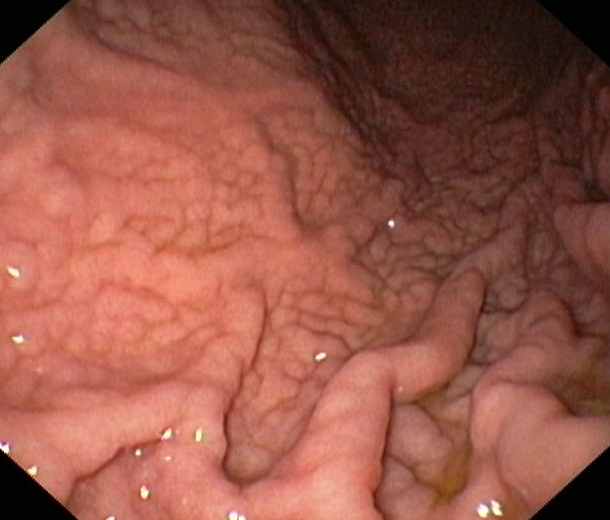

Gastritis caused by a chronic Helicobacter Pylori-infektion